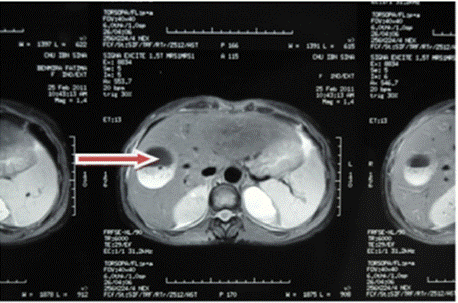

Figure 2: Abdominal MRI C-, frontal section showing a rounded formation

with clear boundaries in the right liver with heterogeneous content.

Ultrasound of the right liver (anterior sector) revealed a heterogeneous cystic image with a thin wall, suggestive of a type IV hydatid cyst. Abdominal CT confirmed a multiloculated cystic lesion containing fatty, calcified, and fluid components, suggestive of a hepatic teratoma. An MRI scan further supported the diagnosis, showing a grossly oval lesion in the hepatic dome measuring 57 × 48 mm. The lesion contained a fluid level with a supernatant displaying T1 hypersignal, T2 hyposignal, and a dependent portion in T1 and T2 isosignal, without enhancement after gadolinium injection — findings suggestive of a modified hydatid cyst.